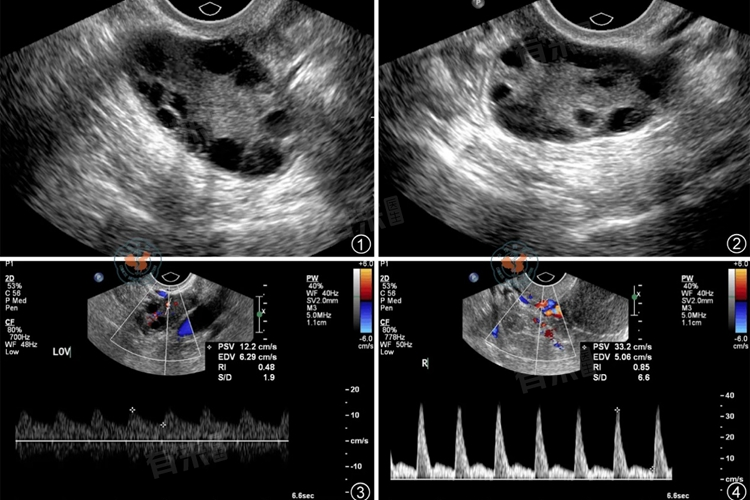

2、B超检查:通过B超检查,观察卵巢的形态和结构,了解是否存在多囊卵巢等异常。